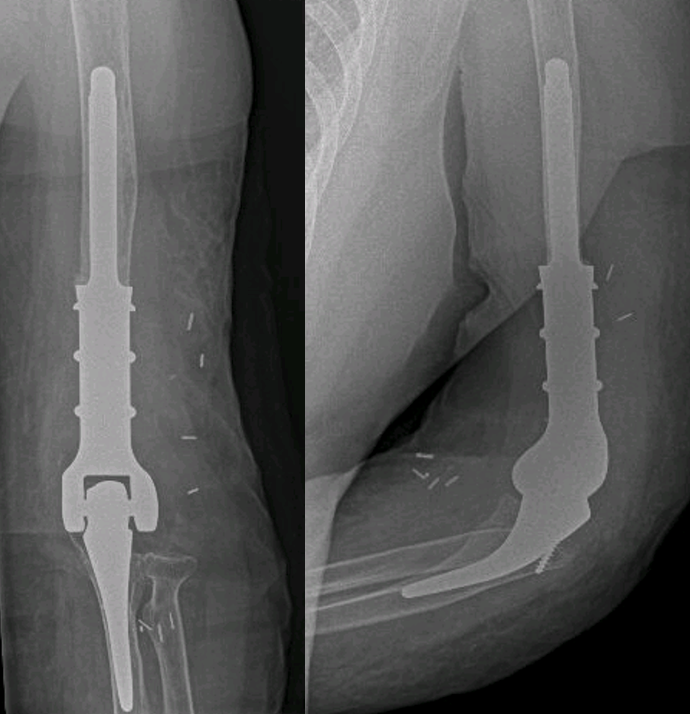

Nos dedicamos a devolver la función y la confianza a tus manos y brazos. Tratamos desde los problemas más frecuentes hasta casos complejos que requieren cirugía avanzada y reconstrucción.